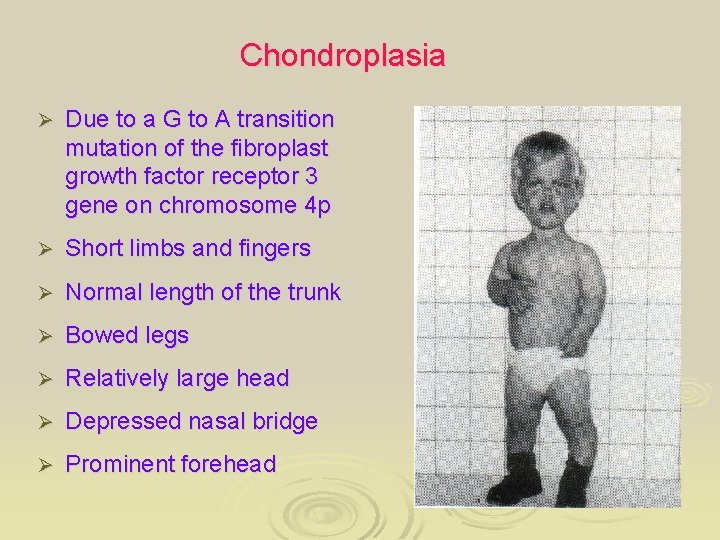

Chondroplasia Ø Due to a G to A transition mutation of the fibroplast growth factor receptor 3 gene on chromosome 4 p Ø Short limbs and fingers Ø Normal length of the trunk Ø Bowed legs Ø Relatively large head Ø Depressed nasal bridge Ø Prominent forehead